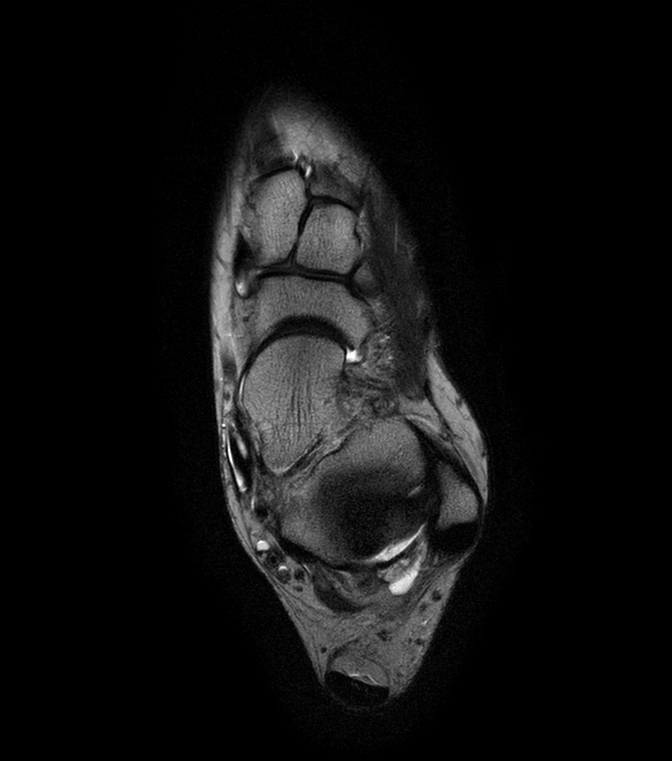

Imaging with the dS 16ch FootAnkle coil

General Hospital Sint Blasius, Dendermonde, Belgium

Patient who was referred for imaging of the achilles tendon